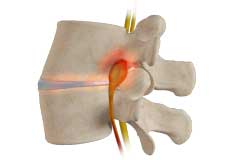

Lumbar Herniated Disc

A herniated disc is a condition in which the outer fibers (annulus) of the intervertebral disc are damaged, causing the soft inner material of the nucleus pulposus to rupture out of its space. It is the most common cause of lower back pain and pain that radiates down the leg (radiculopathy).

Lumbar Disc Herniation

Lumbar disc herniation is the most common cause of lower back pain and leg pain (sciatica). Aging, injury or trauma may cause the annulus fibrosus to tear, resulting in protrusion of the nucleus pulposus. This may compress the spinal nerves and/or spinal canal.

Microdiscectomy is a surgical procedure employed to relieve the pressure over the spinal cord and/or nerve roots, caused by a ruptured (herniated) intervertebral disc. A herniated disc, common in the lower back (lumbar spine) occurs when the inner gelatinous substance of the disc escapes through a tear in the outer, fibrous ring (annulus fibrosis).

Lumbar Discectomy

A lumbar discectomy is a surgical procedure performed to treat a herniated or ruptured disc and relieve pressure on the spinal nerves.